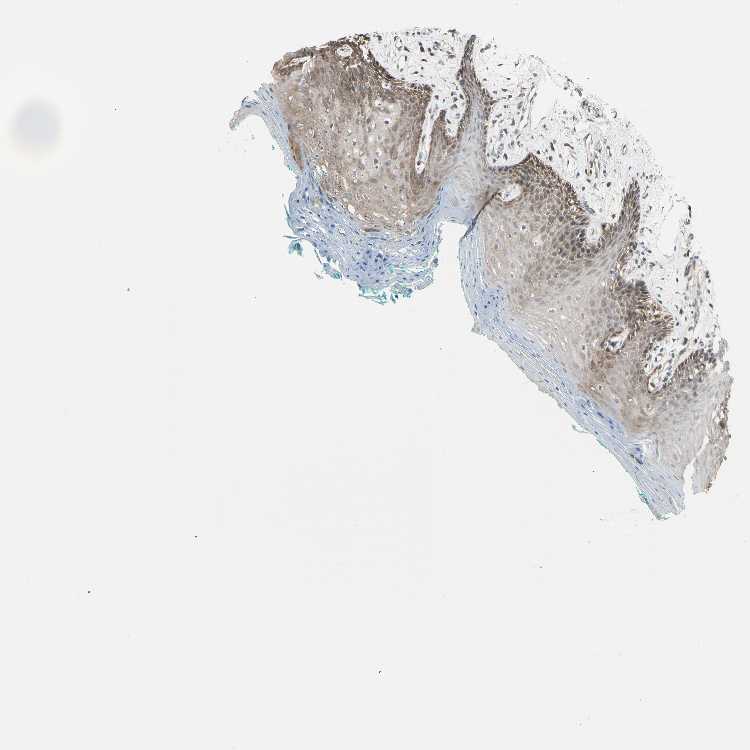

TISSUE PRIMARY DATA ORAL MUCOSA Show tissue menu

ORAL MUCOSA - Antibody stainingi

Antibody staining in the annotated cell types in the current human tissue is reported as not detected, low, medium, or high, based on conventional immunohistochemistry profiling in selected tissues. This score is based on the combination of the staining intensity and fraction of stained cells.

Each image is clickable and will lead to virtual microscopy that enables deeper exploration of all samples and also displays staining intensity scores, fraction scores and subcellular localization as well as patient and tissue information for each sample.

Antibody HPA007925Antibody CAB010286

Squamous epithelial cells MediumLow